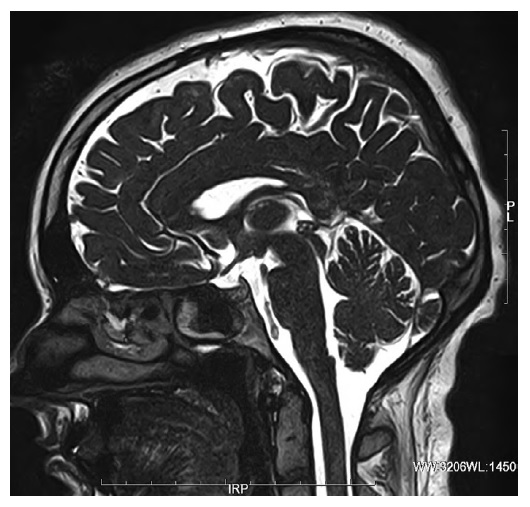

Эпифиз является небольшой малоизученной нейроэндокринной железой, которая располагается в эпиталамусе. В норме эпифиз расположен по сагиттальной линии, прикрепляется к задней части 3-го желудочка, между задней спайкой и дорсальной хабенулярной спайкой (рис. 1).

Рис. 1. МРТ головного мозга, FIESTA-ИП. Срединный сагиттальный срез. Эпифиз нормальной формы и величины. / Fig. 1. Brain MRI, FIESTA sequence. Midline sagittal section. Pineal gland is of normal shape and size.